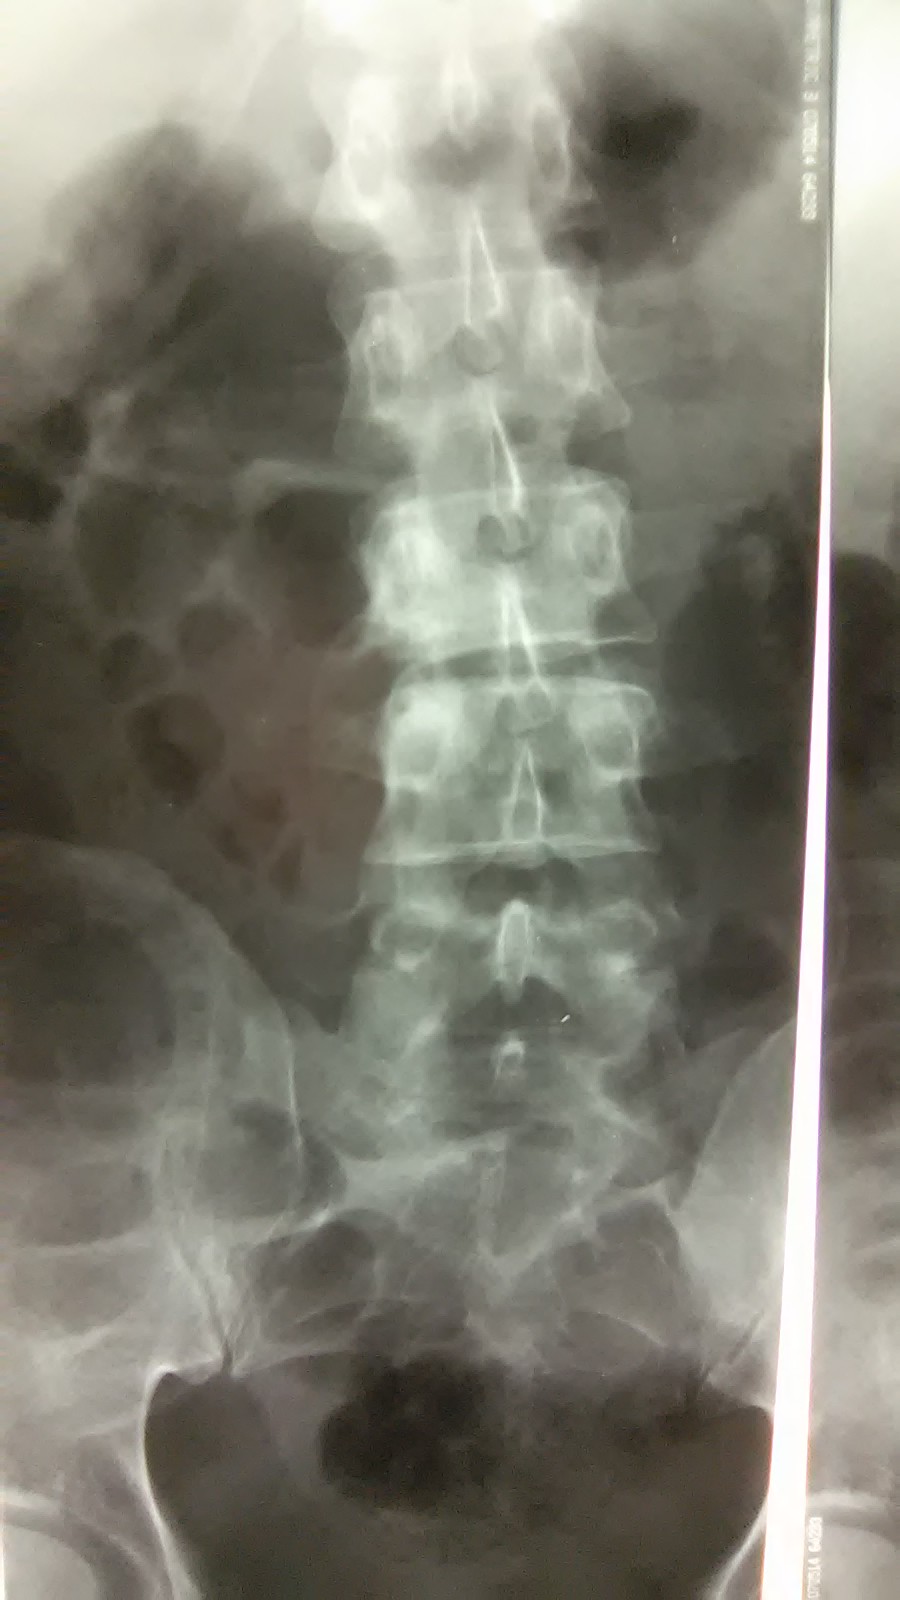

Хотел, видимо, с гнойником разобраться, но его не нашел. Что конкретно делал не знаю. Сегодня пациенту сделали Rtg.

Вложения

WP_20160627_002.jpg

WP_20160627_003.jpg

WP_20160627_004.jpg

Вот только добралась до истории болезни с описанием Rtg-снимков и заключением : "R-признаки спондилита на уровне L3-L4 с краевой деструкцией нижне-правого угла L3. Паравертебральный натечный абсцесс справа?".

Пациента записали на КТ.